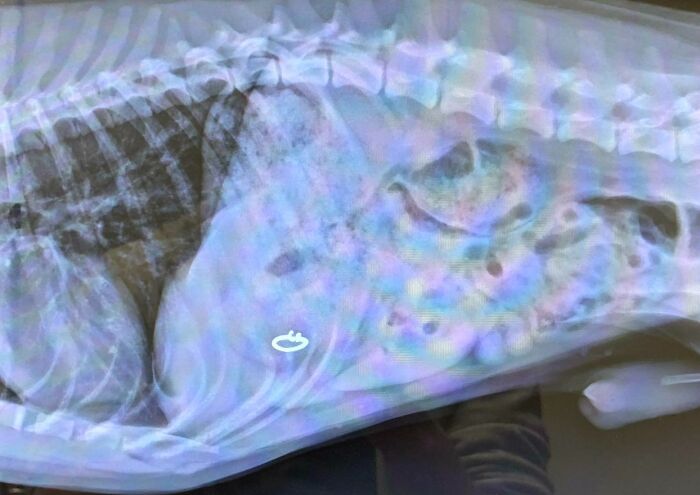

Mi mujer me dijo que tenía algo muy loco que enseñarme después de comer